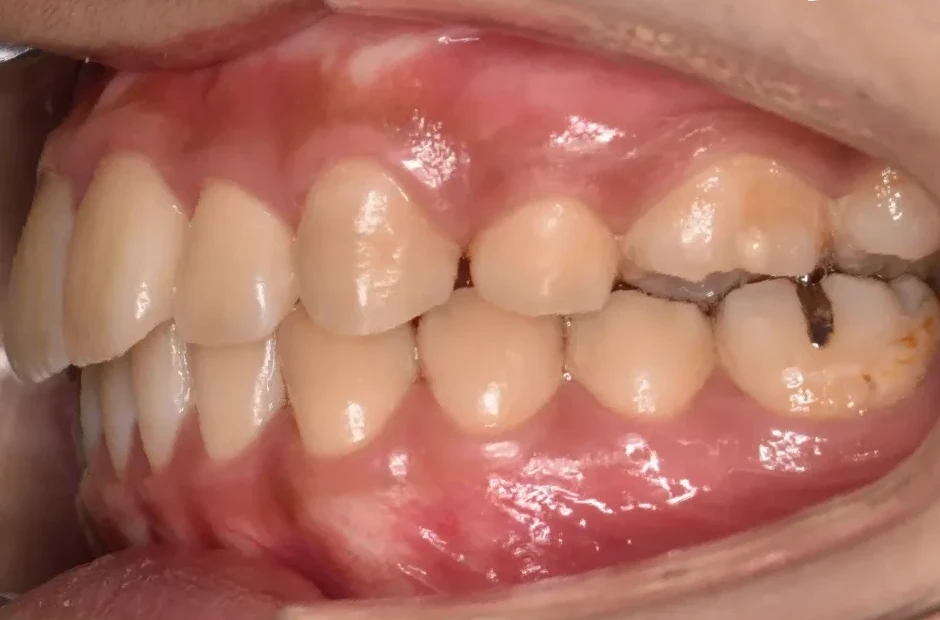

叢生

| 診断名・主訴 | 叢生 |

|---|---|

| 年齢・性別 | 43歳・女性 |

| 治療期間・回数 | 2年7か月 27回 |

| 治療に用いた主な装置 | 舌側矯正 |

| 抜歯部位 | 両顎4,4 |

| 治療費 | 100万円(税抜) |

| リスク・副作用 | 装置による違和感・疼痛・歯肉退縮・歯根吸収・虫歯のリスクなど |

治療前